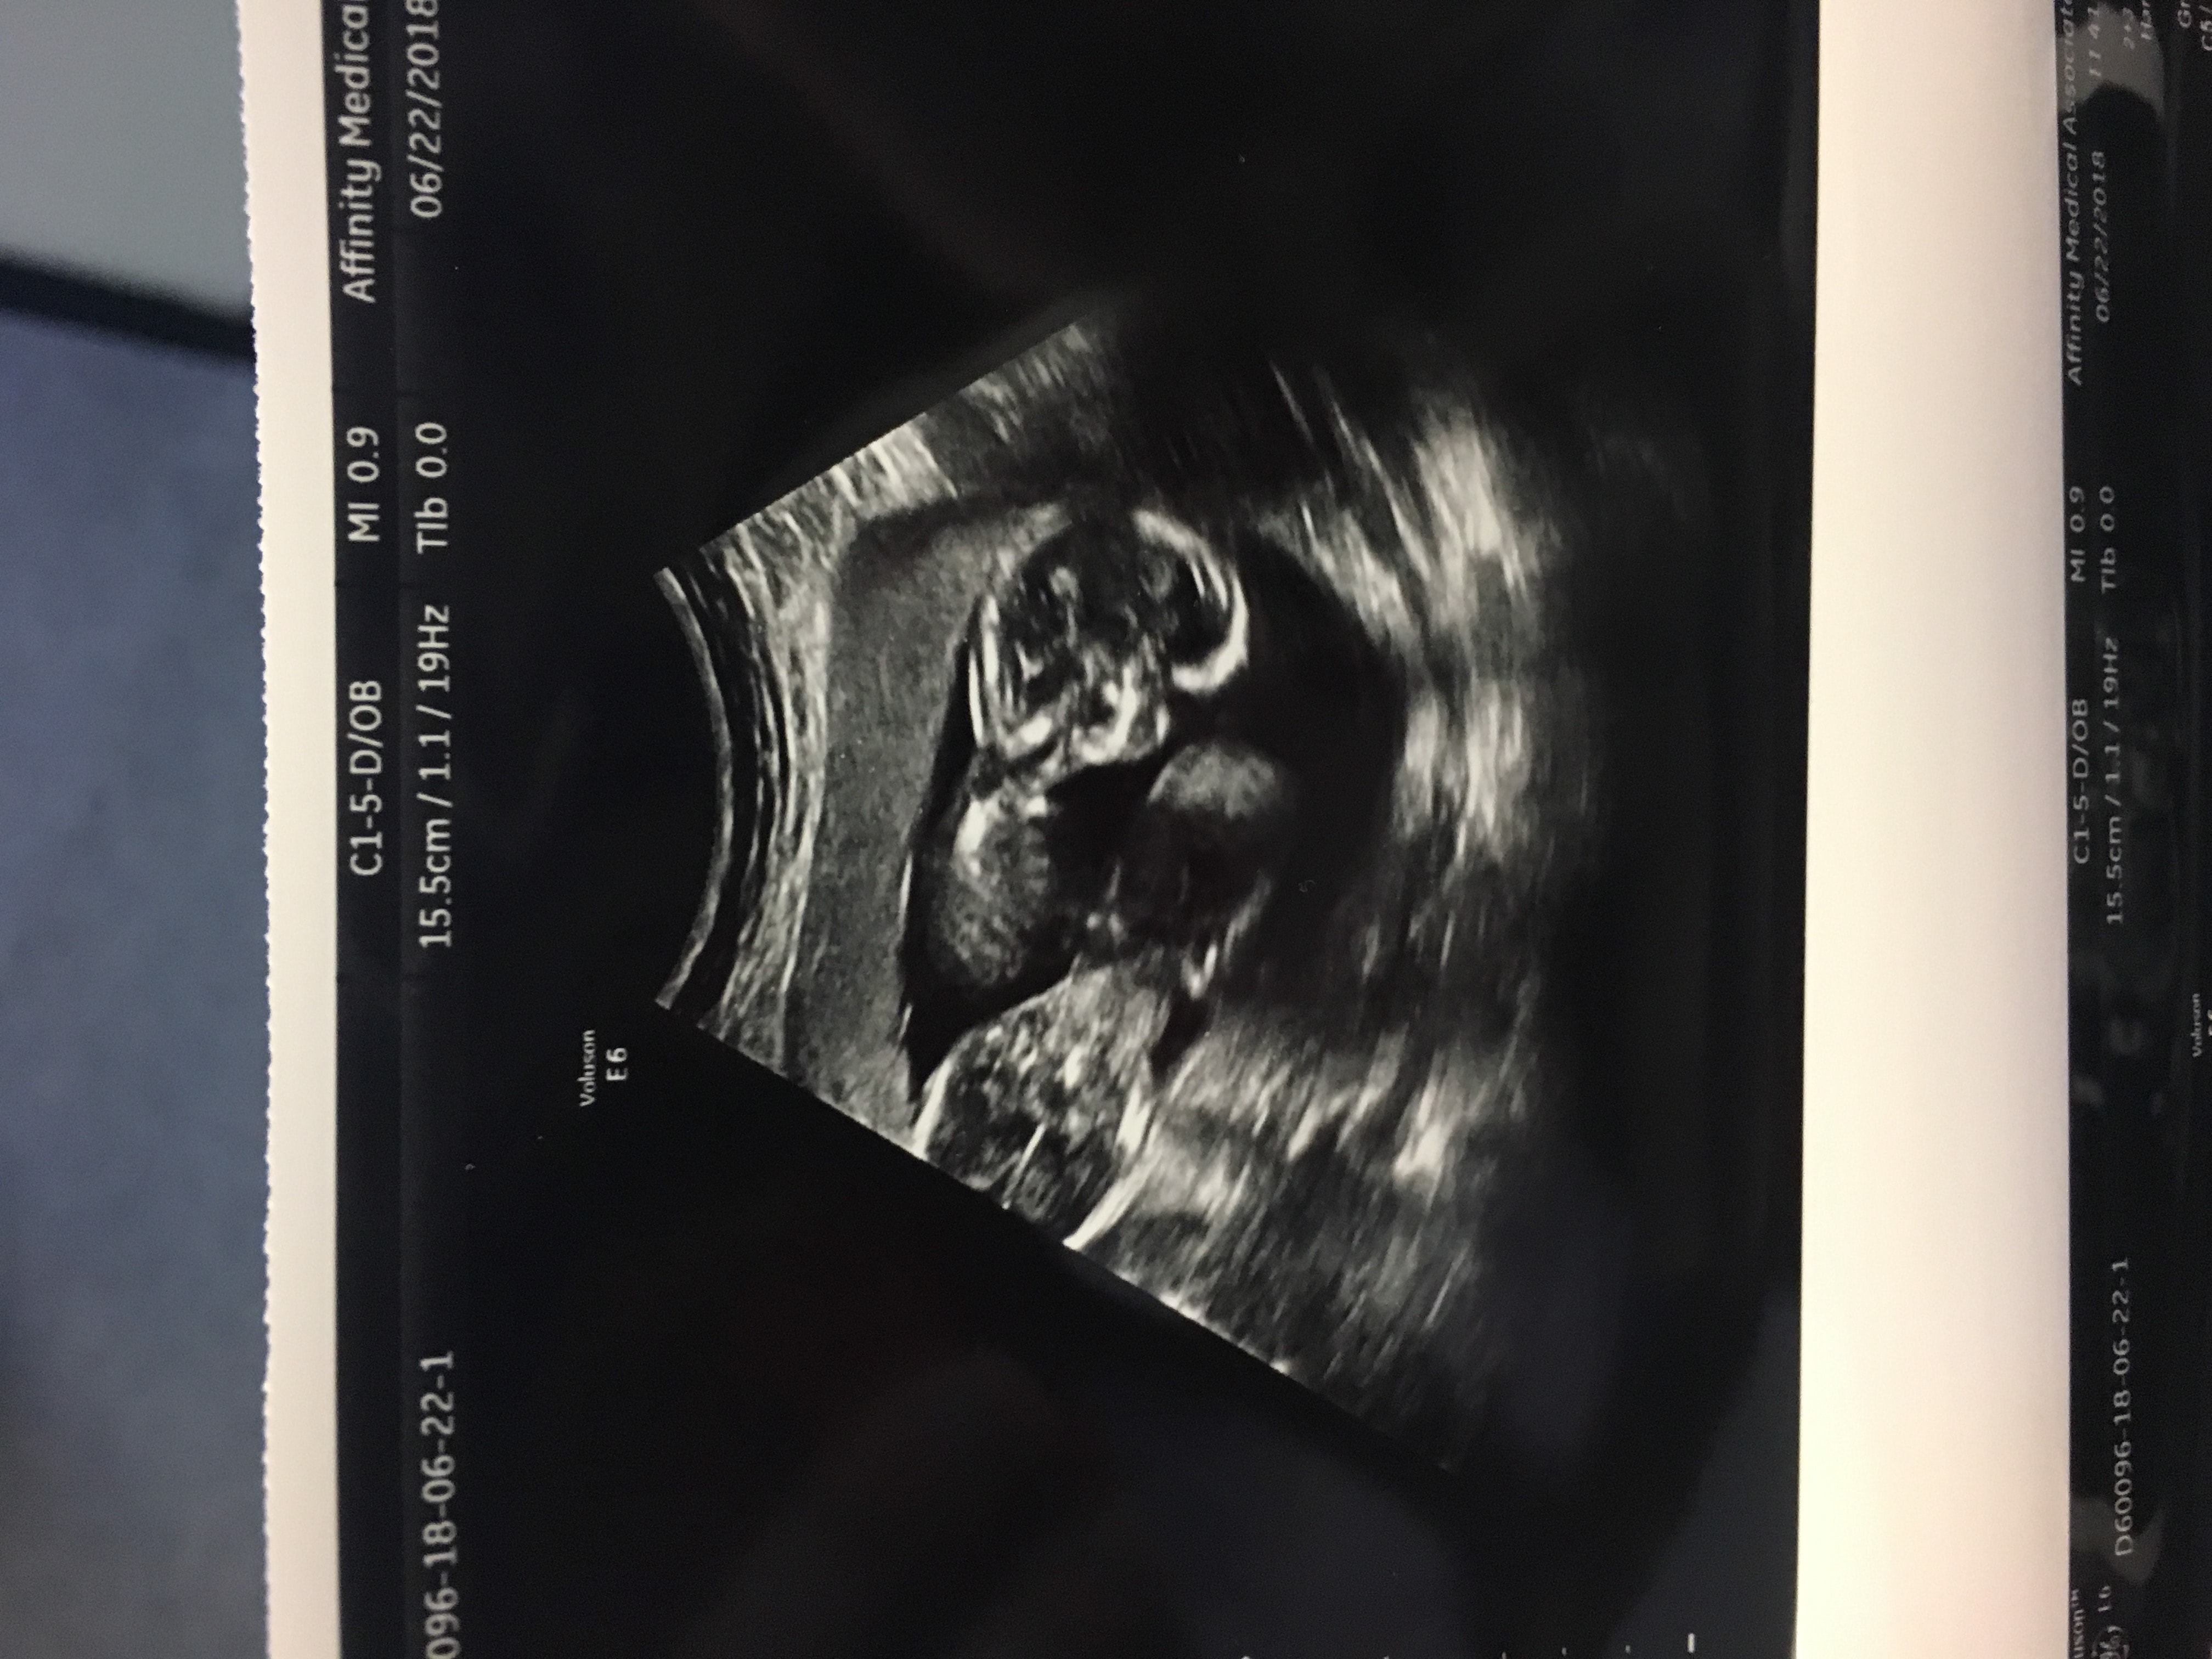

Ultrasound Photos at 15 Weeks Pregnant With Twins